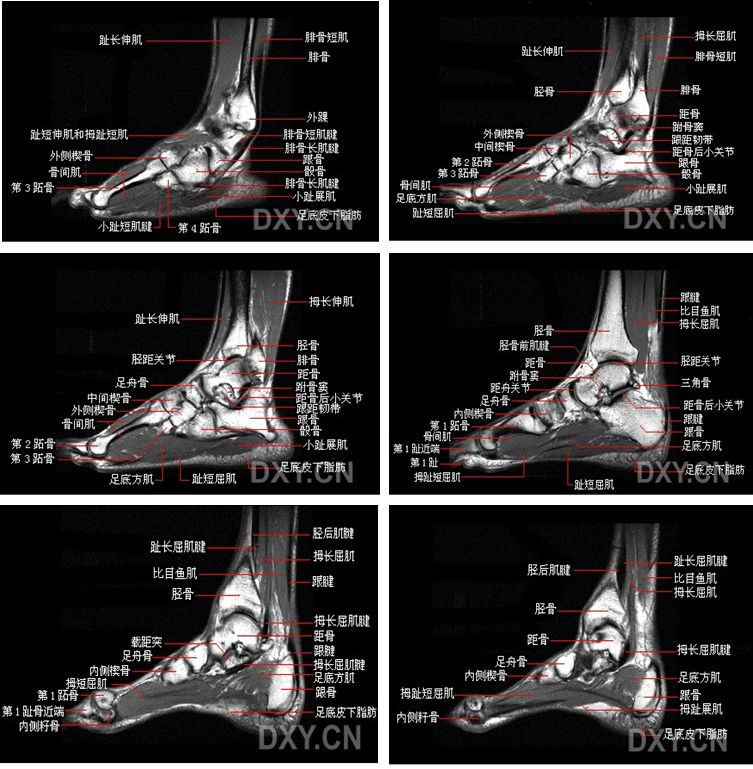

踝关节(anklejoint),由胫、腓骨下端的关节面与距骨滑车构成,故又名距骨小腿关节。胫骨的下关节面及内、外踝关节面共同形成的“冂”形的关节窝,容纳距骨滑车(关节头),由于滑车关节面前宽后窄,当足背屈时,较宽的前部进入窝内,关节稳定;但在跖屈时,如走下坡路时滑车较窄的后部进入窝内,踝关节松动且能作侧方运动,此时踝关节容易发生扭伤,其中以内翻损伤最多见,因为外踝比内踝长而低,可阻止距骨过度外翻。

踝关节解剖